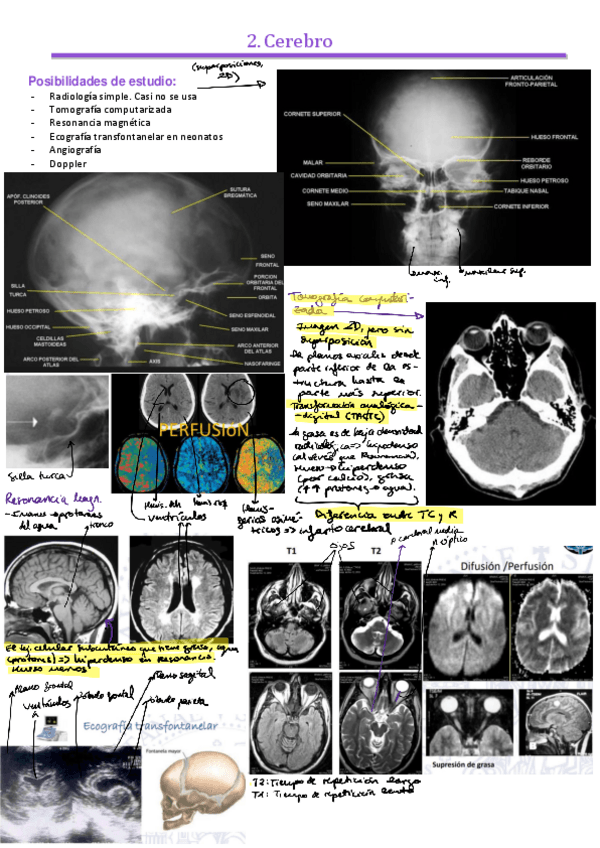

tema-2-cerebro.pdf